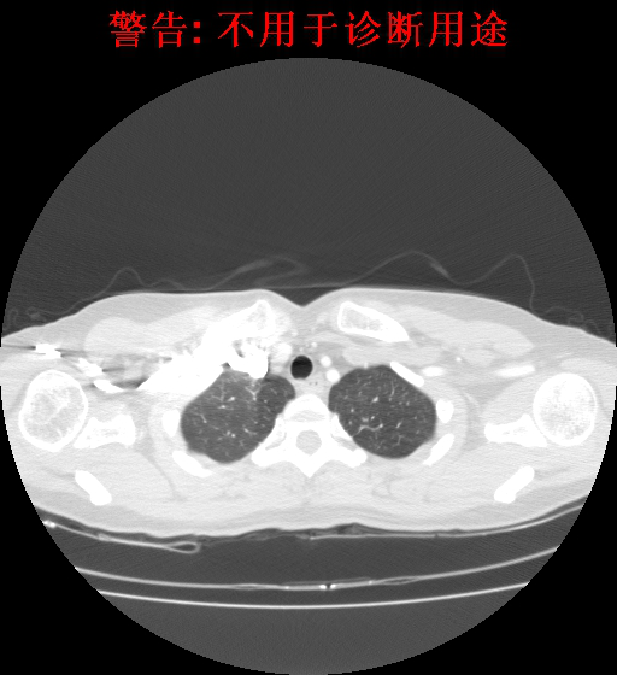

2012-3-21影像